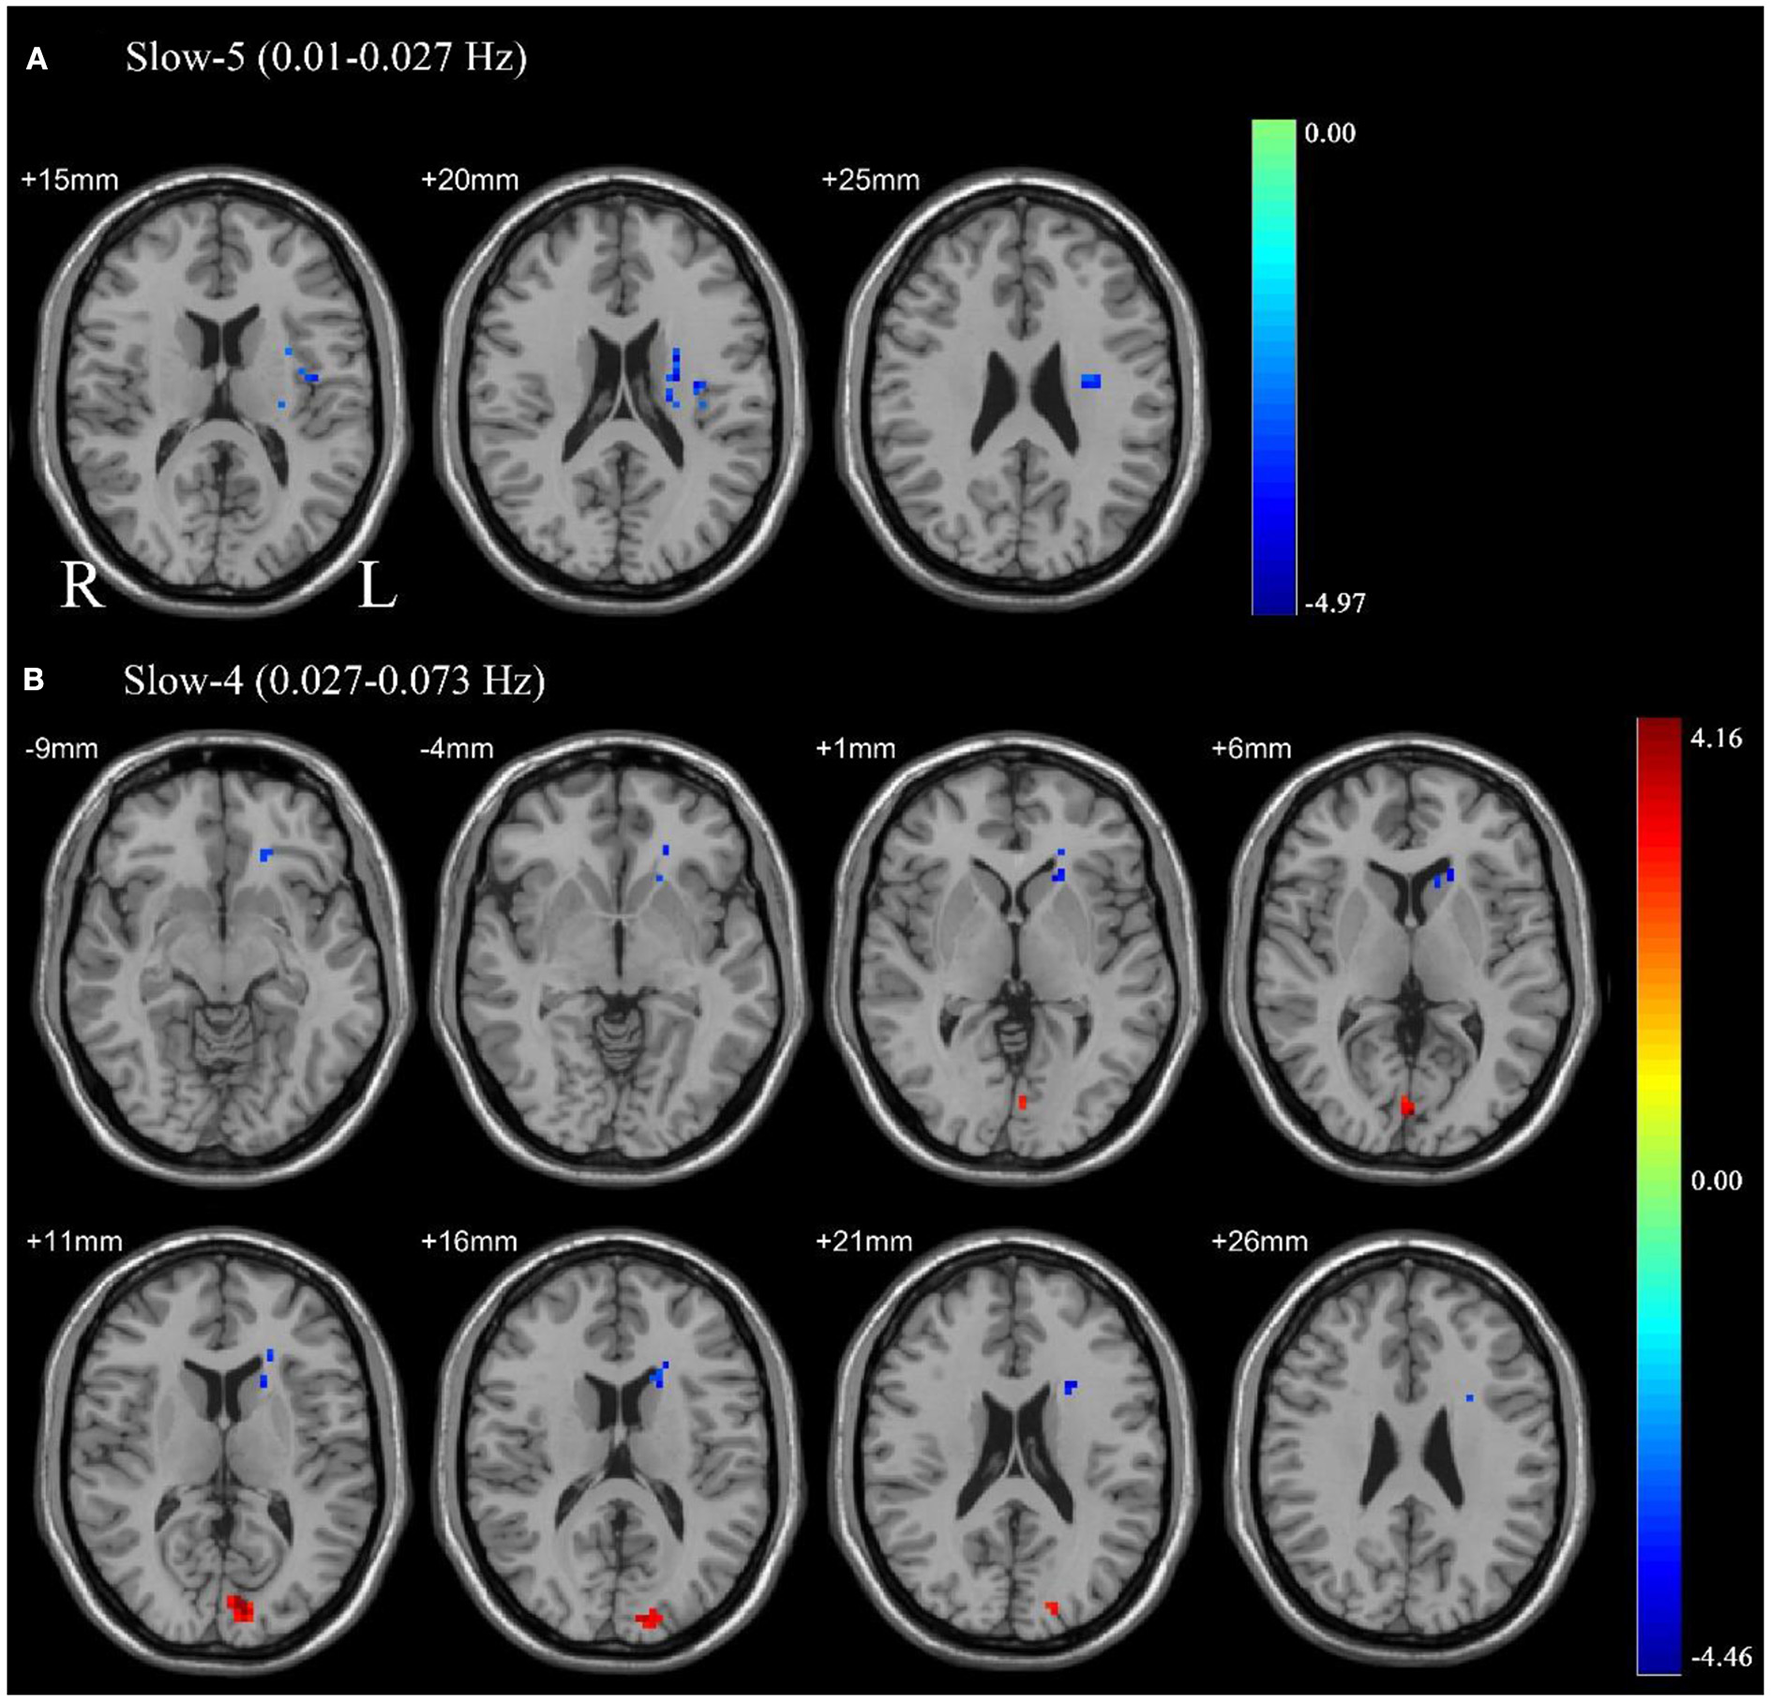

Paired sample t-tests were used to compare the difference in ALFF between pre-CPAP and post-CPAP OSA patients in the slow-4 and slow-5 frequency bands. Figure 2 showed significant differences of ALFF within different frequency bands. The detailed abnormal brain regions are shown in Table 3. We found that after CPAP treatment, ALFF signals in the left insula in the slow-5 and left caudate in the slow-4 increased, but the calcarine in the slow-4 significantly reduced.

Figure 2

Pair sample t-test in the slow-5 frequency band (0.01–0.027 Hz) (A), the slow-4 frequency band (0.027–0.073 Hz) (B). All results were reported at voxel-level p < 0.01 and cluster-level p < 0.05, GRF corrected.